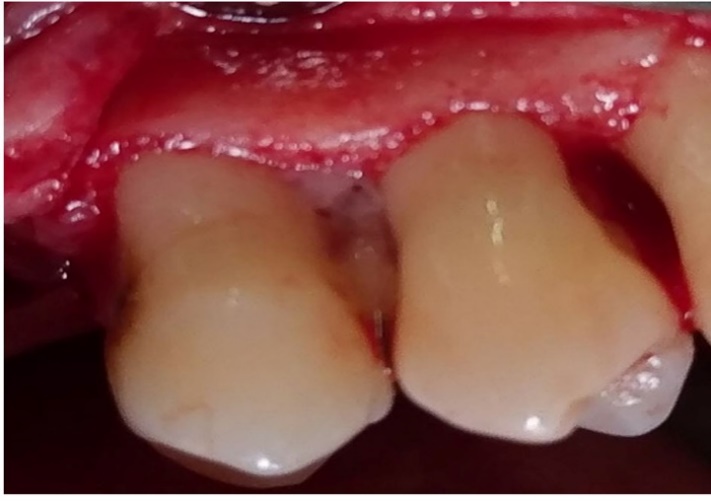

Defect zone containing PRGF.

Then, the flap was sutured in place with silk 3-0 sutures, and the patients were discharged with antibiotic prescription (amoxicillin, 500 mg, TID), the directions for oral hygiene (0.12% chlorhexidine, 5 mL, BID) and with the recalls schedule.

Defect zone containing metformin and PRGF.